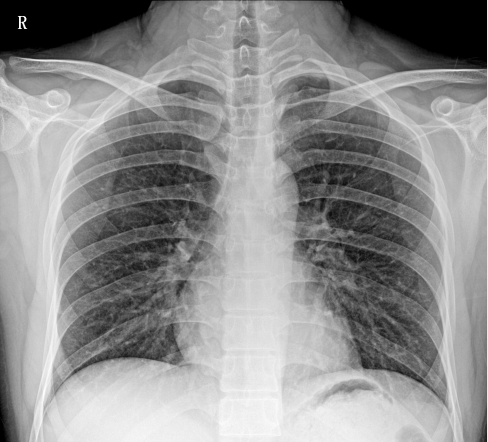

移动DR相比只能固定作业的固定DR相比,移动DR因其便携性、可移动性、操作灵活、摆位方便、占地面积小等优势,成为ICU、发热门诊、防疫病区最为紧急采购的需求设备。在此次新冠治疗中,肺炎影像学诊断是新型冠状病毒感染的重要判断标准之一,CT、DR等医学影像检测设备发挥了重要作用。因此,移动DR被列入国家《重大疫情救治基地应急救治物资储备清单》。下面就大家介绍一下普爱PLX5100型移动DR的产品性能和工作站功能。